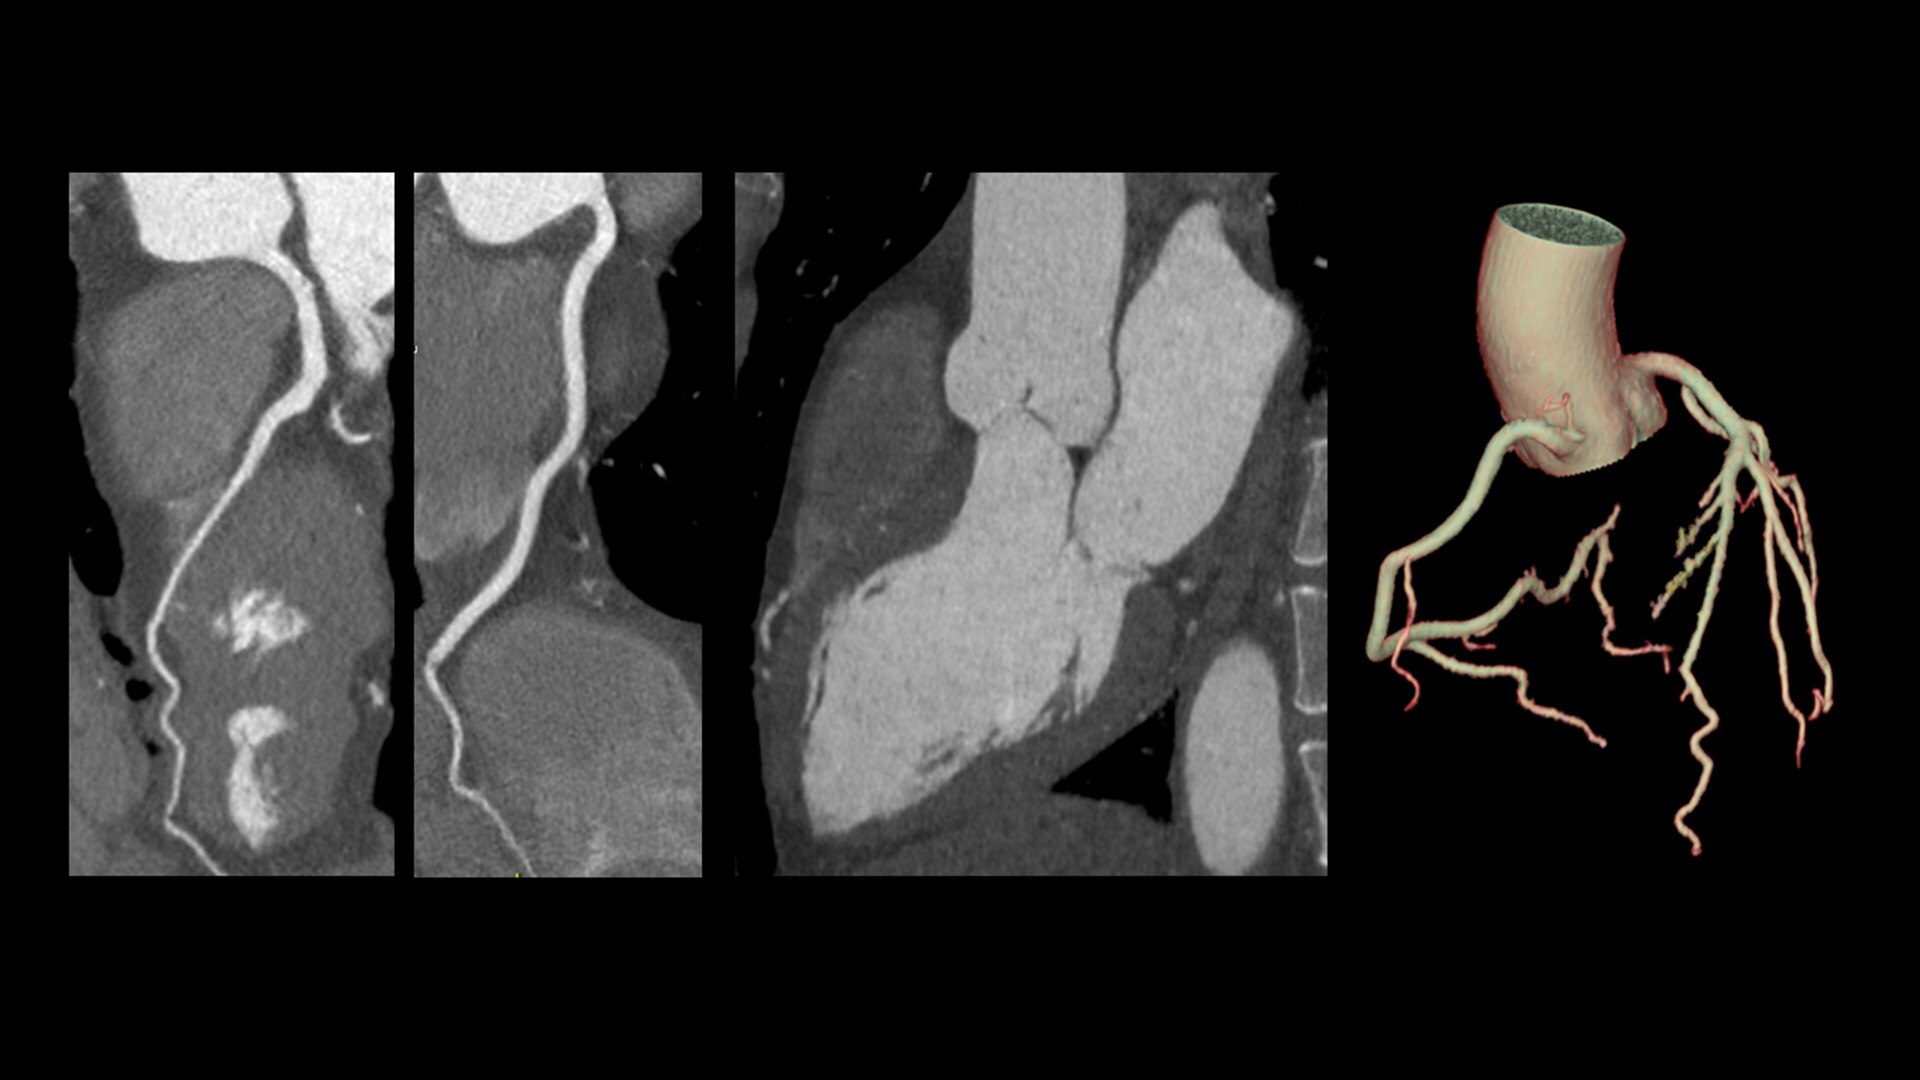

Cardiac CT has become a front-line, non-invasive imaging tool for diagnosing, treatment planning and monitoring of cardiovascular disease

Healthcare providers are striving to improve patient health but are struggling with increasingly complex exams, insufficient or inexperienced staff, and operational and capital efficiency. Revolution™ Vibe, designed to deliver leading-edge technology, features advanced cardiovascular capability. It improves patient access and operational efficiency, prioritizes patient care and supports your facility's growth with lower lifecycle costs.

Unlimited 1-Beat Cardiac is designed to provide consistent, high-quality imaging for accurate diagnoses, even in challenging patients with atrial fibrillation, breath-holding difficulties, heavily calcified coronaries, in-stent restenosis, and situations where an ECG trace is unavailable.